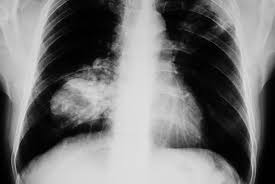

Signs And Symptoms Of Lung Cancer In Female Non Smokers - Pdf Delay In Diagnosis Of Lung Cancer A Case Report / The first symptoms of lung cancer in women are frequently signs of lung adenocarcinoma.. Because these tumors usually grow in the periphery of the lungs, far from the large airways, they're less likely to result in a cough. But even small percentages have an impact: But for nonsmokers between the ages of 40 and 79, more women than men are at risk for developing lung cancer. Be on alert for a new cough that lingers. Learn more about lung cancer symptoms in women.

It affects men more commonly as compared to women. Lung cancer is the second most common form of cancer for both men and women, but there are major differences between outlook and treatment. The most common symptoms of lung cancer are: Brahmer says, patients who have never smoked are shocked and ask, 'why me Because these tumors usually grow in the periphery of the lungs, far from the large airways, they're less likely to result in a cough.

3 from Early signs and symptoms of lung cancer. Most nonsmokers have no early signs of lung cancer, which means it is often not diagnosed until it has spread—but some do have symptoms in the early stages. They may have many symptoms like coughing and breathing difficulty, instead of women who might experience fatigue or back pain as early signs. Symptoms of lung cancer are the same for smokers and nonsmokers. Some people have general symptoms of not feeling well or feeling tired all the time. The latest data show an incidence rate in nonsmoking women ranging from 14.4 to 20.8 percent. The most common symptoms of lung cancer are: (a cough that doesn't go away or gets worse, chest pain that is often worse with deep breathing, coughing or laughing, hoarseness persistent, unexplained loss in weight and loss of appetite, cough with blood, shortness of breath, unexplained fatigue and weakness unexplained, bronchitis or pneumonia that doesn't go away or reappears, and the emergence of breath wheezing).

But even small percentages have an impact: According to the american cancer society, common symptoms of lung cancer include: They may have many symptoms like coughing and breathing difficulty, instead of women who might experience fatigue or back pain as early signs. The most common symptoms of lung cancer are: 8 shortness of breath with activity Early signs of lung cancer include hoarseness, shortness of breath and/or new onset of wheezing. Smoking tobacco is the most common cause of lung cancer but other risk factors are also responsible for lung cancer in non smokers. Early signs and symptoms of lung cancer. Signs and symptoms of lung cancer may include: In 2018, as many as 20% of people who died from lung cancer had. Lung cancer is the most prevalent cancer worldwide. Signs and symptoms of lung cancer typically occur when the disease is advanced. These symptoms can happen with other illnesses.

Learn more about lung cancer symptoms in women. The first symptoms of lung cancer in women are frequently signs of lung adenocarcinoma. A cough that won't quit or changes. Among never smokers, the early signs of lung cancer are often subtle and nonspecific, such as shortness of breath that is only present with activity or fatigue. These are similar to the symptoms in smokers and may include the following: 1 for this reason, and because there isn't yet a screening test available for never smokers, lung cancers are frequently diagnosed in more advanced stages of the disease. Smoking tobacco is the most common cause of lung cancer but other risk factors are also responsible for lung cancer in non smokers. These symptoms can happen with other illnesses. Nonsmokers typically experience nonspecific symptoms such as fatigue or shortness of breath with activity. In the study, lung cancer in women is more likely to be classified as adenocarcinoma while men are likelier to have squamous cell carcinomas. Some people cough frequently, cough up blood, or have chest pain, wheezing, or shortness of breath. The symptoms of lung cancer in women are sometimes different than in men, largely because both sexes tend to get different types of lung cancer. Symptoms of lung cancer are the same for smokers and nonsmokers.

For one thing, the most common lung cancer in women is adenocarcinoma; But even small percentages have an impact: The early signs of lung cancer in a nonsmoker are different from those who smoke. These are similar to the symptoms in smokers and may include the following: (a cough that doesn't go away or gets worse, chest pain that is often worse with deep breathing, coughing or laughing, hoarseness persistent, unexplained loss in weight and loss of appetite, cough with blood, shortness of breath, unexplained fatigue and weakness unexplained, bronchitis or pneumonia that doesn't go away or reappears, and the emergence of breath wheezing).

According to the american cancer society, common symptoms of lung cancer include: Among never smokers, the early signs of lung cancer are often subtle and nonspecific, such as shortness of breath that is only present with activity or fatigue. Early signs of lung cancer include hoarseness, shortness of breath and/or new onset of wheezing. A cough that won't quit or changes. The first symptoms of lung cancer in women are frequently signs of lung adenocarcinoma. In men, the most common kind of lung cancer is squamous cell carcinoma, which tends to produce more symptoms (see above). (a cough that doesn't go away or gets worse, chest pain that is often worse with deep breathing, coughing or laughing, hoarseness persistent, unexplained loss in weight and loss of appetite, cough with blood, shortness of breath, unexplained fatigue and weakness unexplained, bronchitis or pneumonia that doesn't go away or reappears, and the emergence of breath wheezing). A cough that doesn't go away or gets worse over time Symptoms of lung cancer are the same for smokers and nonsmokers. Brahmer says, patients who have never smoked are shocked and ask, 'why me For one thing, the most common lung cancer in women is adenocarcinoma; Here, we describe possible genetic and hormonal factors, treatments, and more. 1 for this reason, and because there isn't yet a screening test available for never smokers, lung cancers are frequently diagnosed in more advanced stages of the disease.